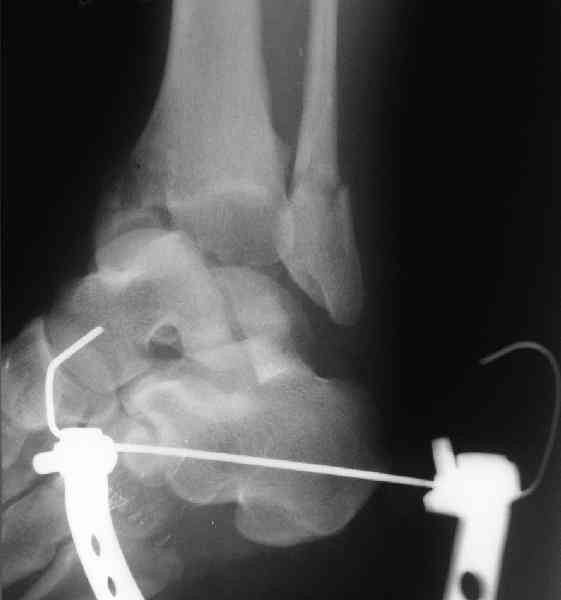

Re: повреждение таранной кости

послал Maxim Agalakov 18 Июнь 2007, 22:59

Для оценки состояния нужны дополнительные исследования, например

> Canale или Broden ренгенограммы

повторили рентгенограммы и доделали проекции, к единому мнению все еще не пришли